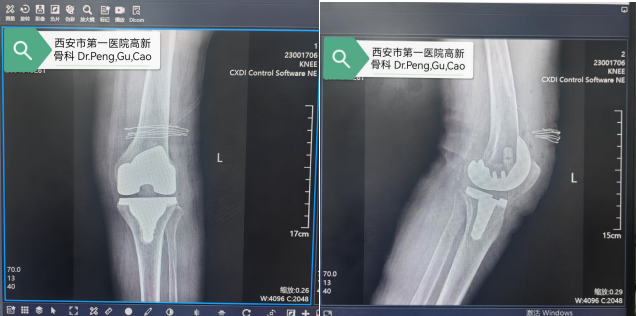

骨科顾始伟副主任医师考虑到患者基础疾病多、手术风险高,立即与关节专家彭主任组织心血管内科、内分泌科、麻醉科等多学科专家会诊,制定个性化术前方案,并精准测算截骨角度与假体大小,制定“毫米级”手术方案。手术当天,在麻醉科、手术室密切配合下,彭主任主刀,手术历时不到1小时,出血量远低于预期,未出现术中并发症。

术后,团队采用“循序渐进、个性化康复”原则,从踝泵运动到关节屈伸、行走训练全程跟踪指导。目前胡阿姨膝关节疼痛完全缓解,腿型从“O”型变笔直,已能自主行走。